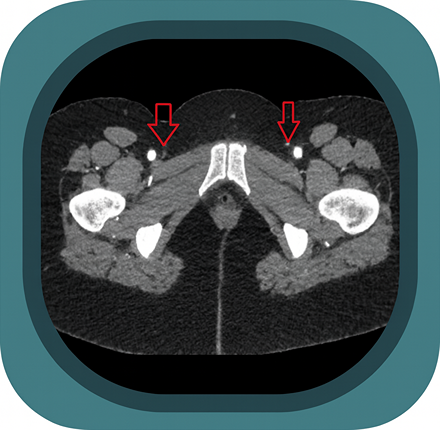

Explore full-body CT anatomy in 3 planes. Our high-resolution, carefully labelled images reveal micro-anatomy—ideal for radiologists, radiographers and surgeons.